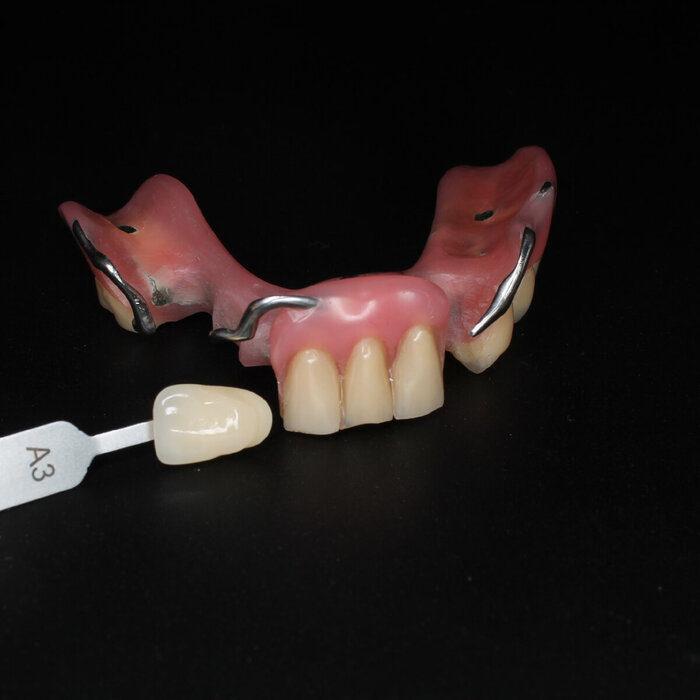

Временный адаптационный протез с опорой на 6 имплантов.

Временный адаптационный протез с опорой на 6 имплантов

Временный адаптационный протез с опорой на 6 имплантов. Нижняя челюсть.